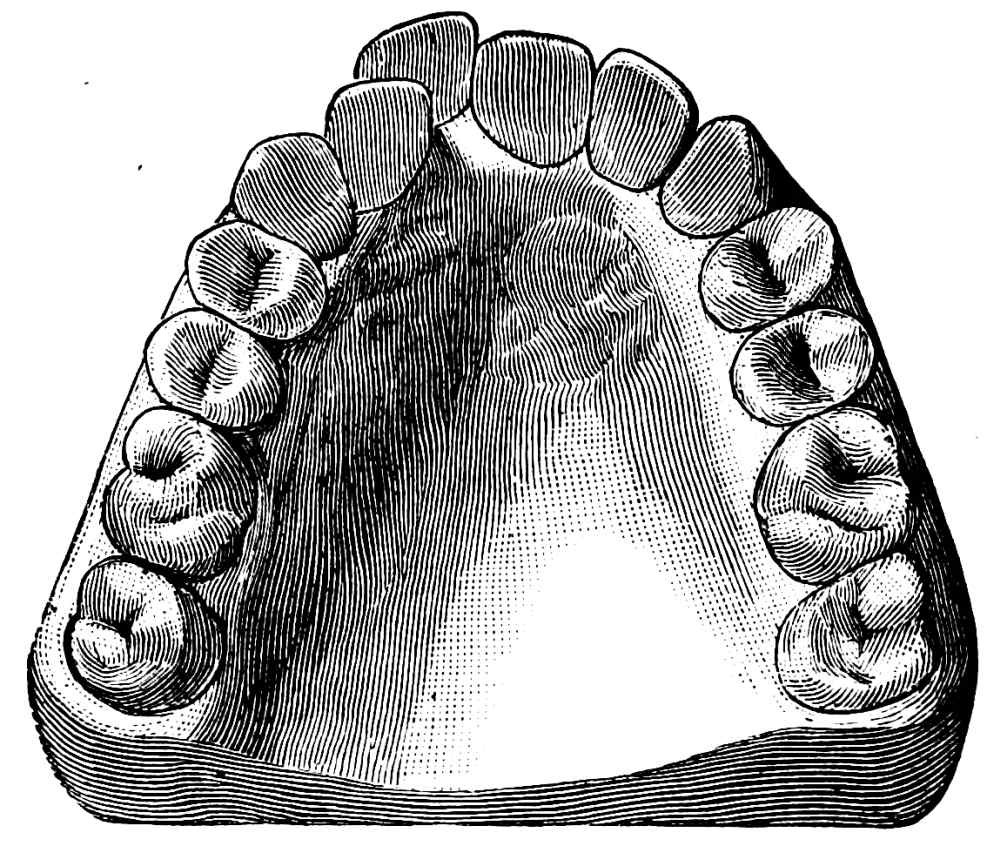

A correct acquaintance with the disposition of the alveoli of the teeth is of importance for skilful and successful operating. Fig. 15 gives a general idea of the appearance of the alveoli, but it is needless to say that a full knowledge can only be really obtained by a careful study of the bones themselves; by this means, too, some idea of the strength of different portions of the alveolar borders can be obtained—a matter of some moment when applying force in the process of removing a tooth from its socket. The points to be specially noted in the maxilla are the thinness of the outer alveolar wall as compared with the inner, the prominence of the canine socket, and the cancellous character of the bone in the region of the third molar. In the mandible the outer alveolar border will be seen to be thinner than the inner, with the exception of that portion in the region of the{13}

Fig. 15.

From the “American System of Dentistry.”

third, and often of the second molar; another fact worthy of attention is that at the posterior portion{14} of the socket of the third molar the bone is moderately dense.